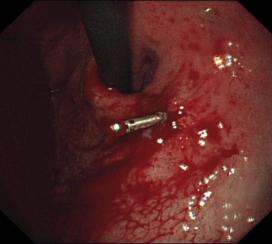

胃底潰瘍并出血止血術(shù)

食管曲張靜脈出血套扎術(shù)